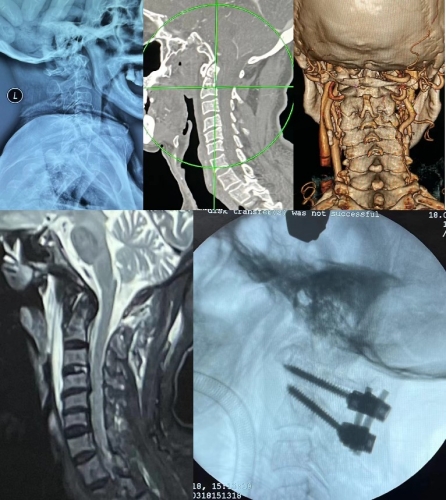

患者陈某,男性,89岁,3月18日在山上砍竹子时不慎摔倒,导致头部血流不止,同时伴脖子后颈部疼痛,立即被送到常宁市人民医院就诊,该院主治医师张冉接诊了患者。行影像学检查后发现患者的寰椎前弓及后弓、枢椎齿状突基底部发生骨折,另外患者左侧椎动脉有闭塞,严重影响脑部供血。根据患者的病情及检查,张医师认为患者必须要尽快手术复位,不手术可能会危及生命,同时要注意防止移位造成二次损伤。但是由于患者受伤部位特殊,手术复杂,手术难度及风险极大,常宁市人民医院骨外科尚无医师能开展该手术。为了更快更好地挽救患者的生命,常宁市人民医院骨外科紧急通过新湘雅专科联盟平台与中南大学湘雅三医院专家取得联系,并邀请湘雅三医院脊柱外科专家前往指导救治。

邓幼文、李劲松在接到紧急邀请后,立马进行了远程会诊,在详细了解患者病情后,明确了患者诊断“寰椎Jefferson骨折合并齿状突2型骨折”,并一致认为患者目前的情况已是不幸中的万幸,此类骨折稍有不慎就会导致死亡,为了避免患者出现二次损伤同时为患者争取救治时间,邓幼文主任让当地医师做好术前准备的同时,带领李劲松组长紧急奔赴常宁市人民医院骨外科。

3月18日下午,邓幼文、李劲松与常宁市人民医院骨外科团队施行手术。术中发现,患者的寰枢椎弓根最宽处直径只有数毫米,手术操作空间极为狭小,内固定的螺钉植入稍偏外就会损伤椎动脉,导致大出血死亡或大面积脑梗,而螺钉稍偏内就会损伤脊髓导致高位瘫痪。经过2个小时的紧张手术,顺利完成了寰椎前弓及后弓、枢椎齿状突基底部切开复位+椎管减压+植骨+螺钉内固定。术后患者颈痛消失,生命体征平稳。患者家属对湘雅三医院专家紧急救援表示感谢,“医生和我说,老爷子要是转运到上级医院,不仅耽误了最佳治疗时间,而且路上稍有意外就可能致命,幸好人民医院和湘雅三医院有合作,让我们在家门口就把这个大手术做了。”目前患者正在稳步康复中。